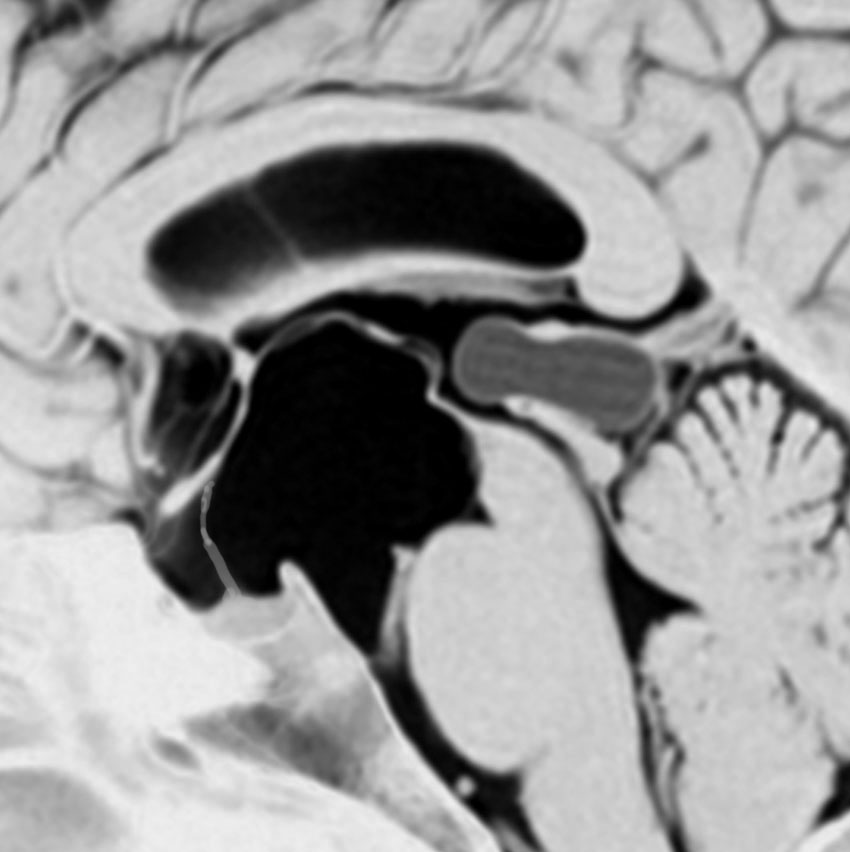

トルコ鞍内くも膜のう胞:先天性無症候性

偶然に発見されたものです,下垂体柄(黄色の矢印)がすごく伸びていて下垂体組織が扁平化していますが,先天性と思われ無症状です。何も治療しないでほっておきます。